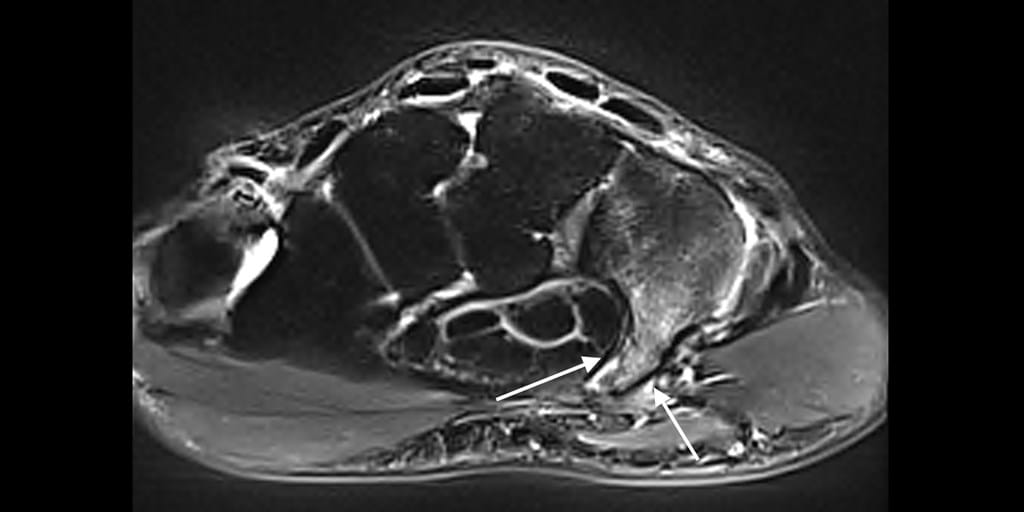

From www.ajronline.org